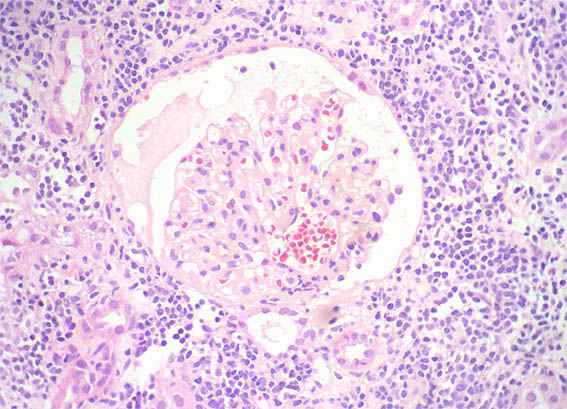

Figure 2. PAS, X400.